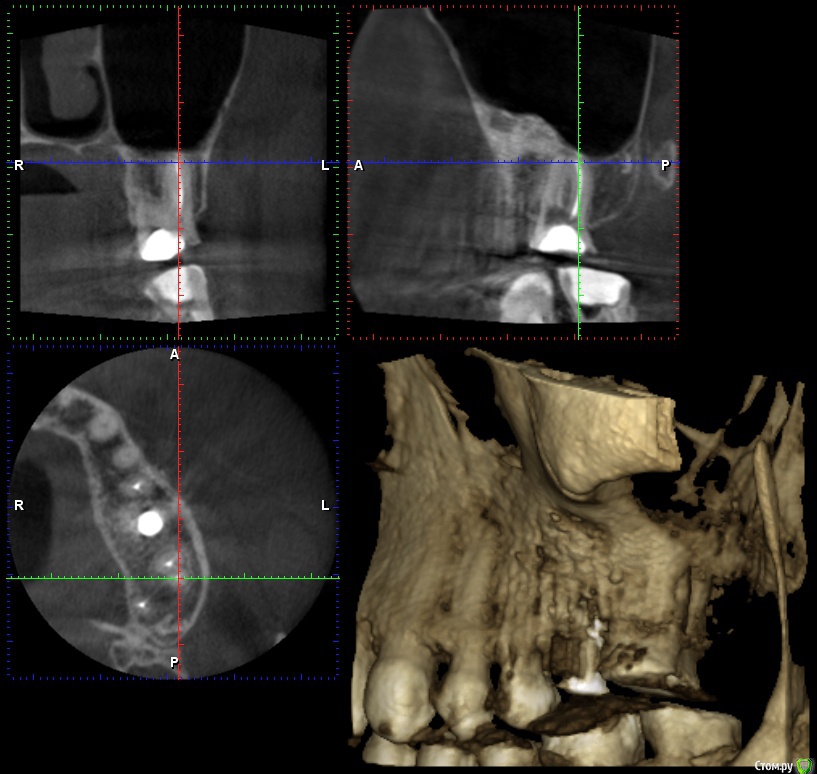

wladdX Опубликовано 26 января, 2017 Поделиться Опубликовано 26 января, 2017 Несколько скринов 2-й сегмент. Ссылка на комментарий

wladdX Опубликовано 26 января, 2017 Поделиться Опубликовано 26 января, 2017 (изменено) 3-й сегмент. Изменено 26 января, 2017 пользователем wladdX Ссылка на комментарий